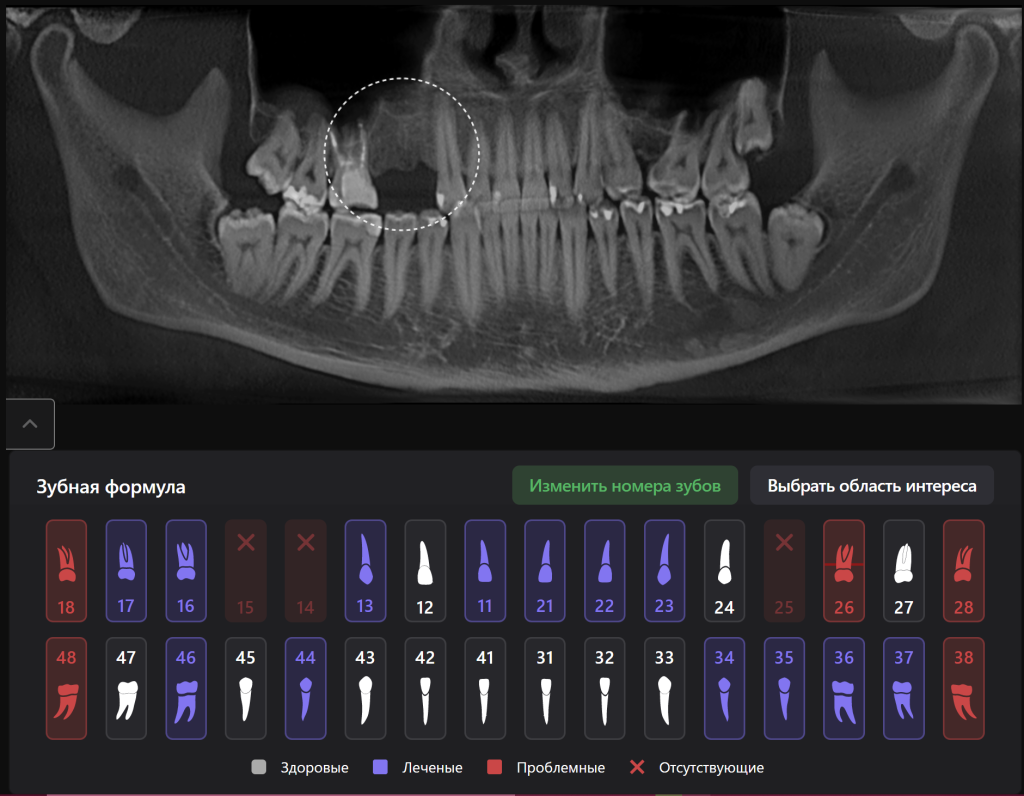

Давайте рассмотрим возможности Diagnocat на примере клинического случая с планированием имплантации на месте отсутствующих зубов 1.4 и 1.5

«Имплантологический отчет», созданный искусственным интеллектом Diagnocat, помогает определить оптимальные размер и расположение имплантата в соответствии с индивидуальными особенностями анатомии